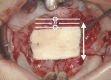

The purpose of this study was to introduce a modification of the Furlow double-opposing Z-plasty (DOZ)-the square-root palatoplasty (SRP)-and critically evaluate outcomes compared to children who underwent straight-line repair (SLR).

Conclusions: This study describes and evaluates outcomes following a modified-Furlow DOZ technique-the SRP. After adjusting for Veau classification, age, and gender in nonsyndromic children, SRP is associated with significantly less speech delay/deficits, NAE, articulation errors, and need for secondary speech surgery when compared to children who underwent SLR.